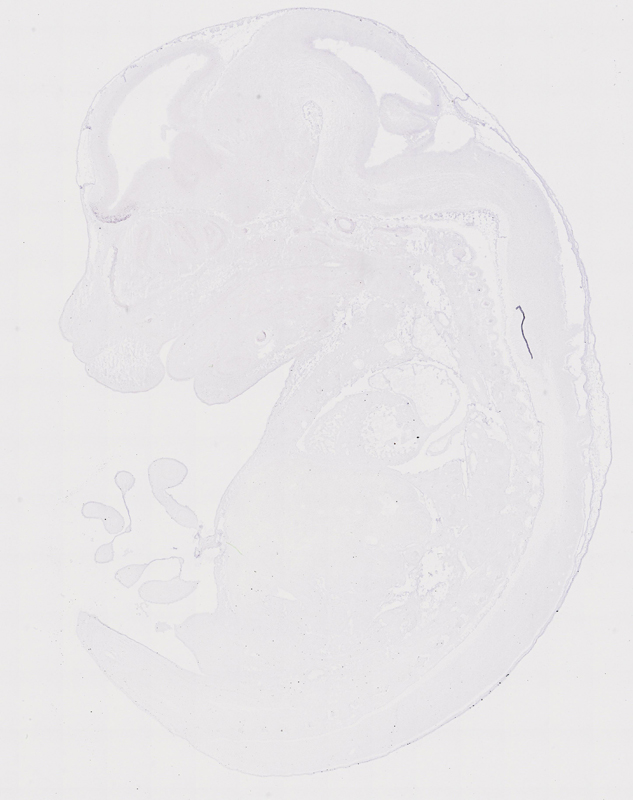

Expression Overview

early conceptus

embryo ectoderm

embryo endoderm

embryo mesoderm

embryo mesenchyme

extraembryonic component

alimentary system

auditory system

branchial arches

cardiovascular system

connective tissue

endocrine system

exocrine system

hemolymphoid system

integumental system

limbs

liver and biliary system

musculoskeletal system

nervous system

olfactory system

reproductive system

respiratory system

urinary system

visual system

Click cells to view annotations.